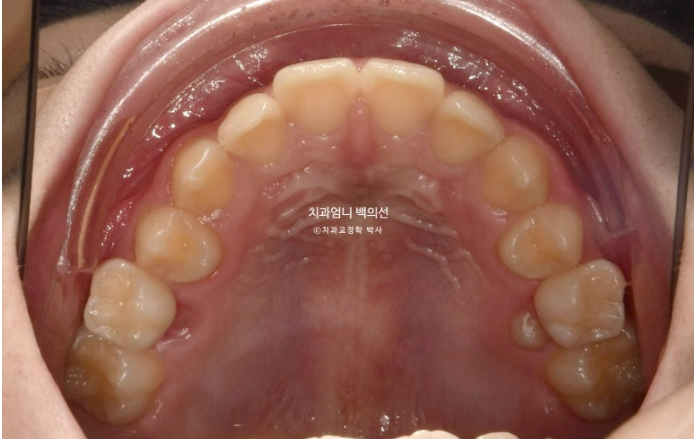

악궁모양은 예뻐졌습니다.

24.03~25.05

치근평행도는 좋고 치근흡수는 없습니다.

치아 이동속도는 빠르고 교정 부작용이 적은 것은 어린이교정의 큰 장점입니다.